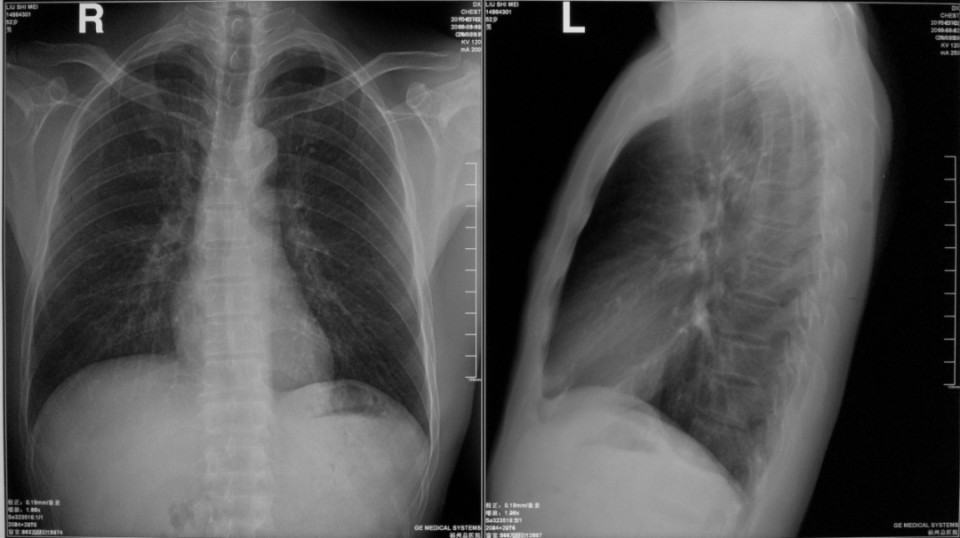

胸部右侧位片

图片

胸部双斜位片